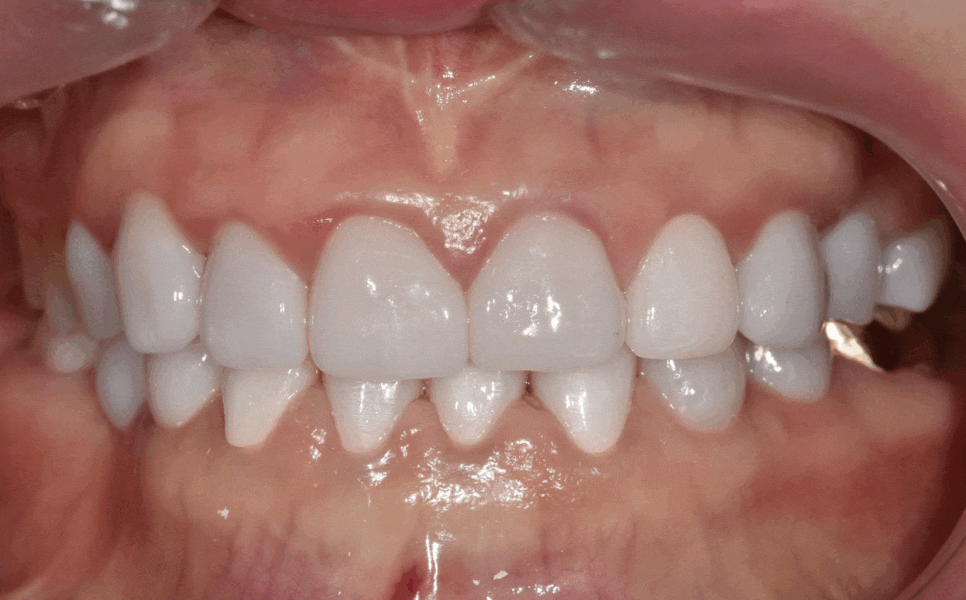

그렇게 최종 완성된 치아

누런 치아 연예인치아 처럼 하얗게 만들 수 있나요?

이런 극적인 변화는 치아미백으로는 절대 불가능합니다.

반면 크라운은 색이 변하지 않아 영구적으로 하얀색을 유지하기 때문에 만족도가 높습니다.

완성 후 환자분의 얼굴 전체 인상이 환해졌습니다.